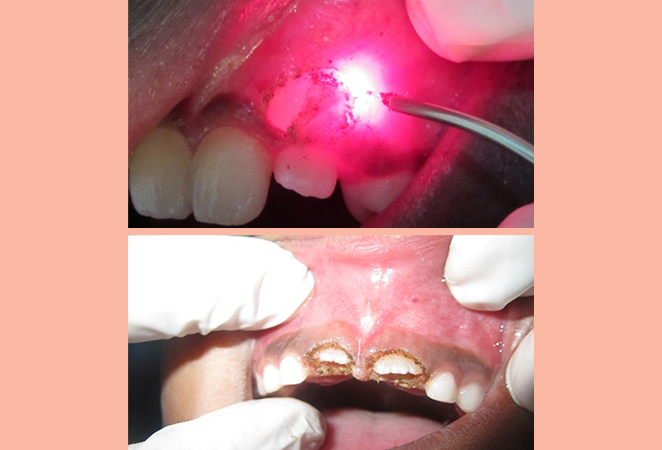

Tooth exposure surgery refers to a procedure which is performed in cases where a tooth has failed to erupt properly. With laser, the tissue over the unerupted tooth (both hard and soft) can be removed easily without bleeding or pain